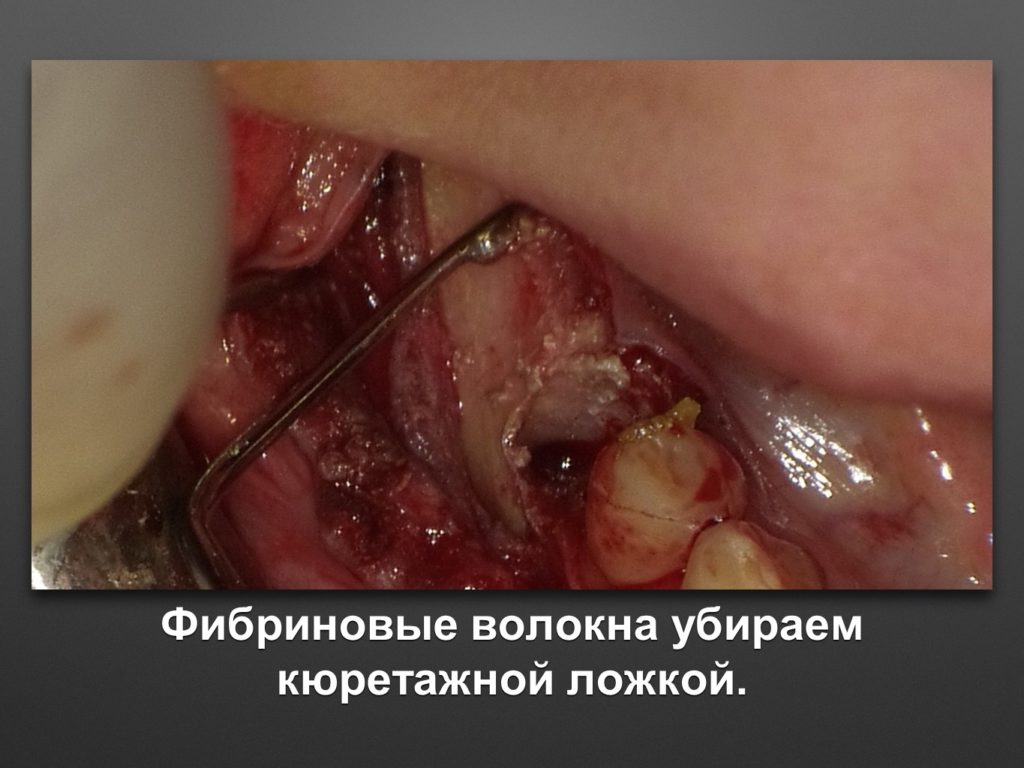

КУПИТЬ КЮРЕТАЖНУЮ ЛОЖКУ KOHLER 3088